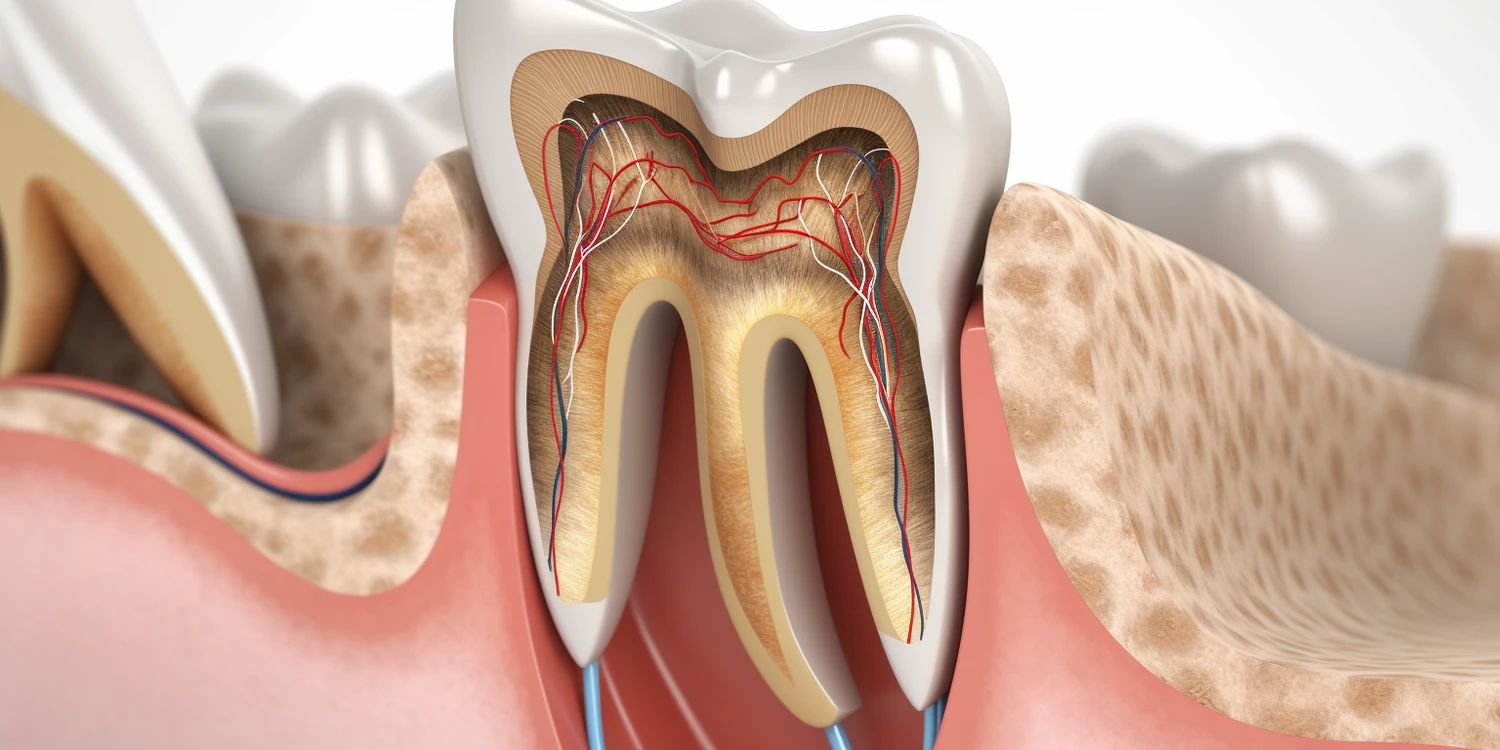

Porównując dentystów do innych specjalistów medycznych, warto zwrócić uwagę na różnice i podobieństwa w zakresie wykształcenia oraz kompetencji. Lekarze różnych specjalizacji przechodzą długotrwały proces kształcenia, który obejmuje studia medyczne oraz staż podyplomowy. Podobnie jak lekarze ogólni czy specjaliści tacy jak kardiolodzy czy ortopedzi, dentyści również muszą zdobywać wiedzę teoretyczną oraz praktyczne umiejętności potrzebne do wykonywania swojego zawodu. Różnica polega jednak na tym, że stomatologia koncentruje się głównie na jamie ustnej oraz powiązanych strukturach anatomicznych. Dentyści są wyspecjalizowani w diagnozowaniu i leczeniu problemów związanych z uzębieniem oraz tkankami miękkimi jamy ustnej. Z drugiej strony lekarze innych specjalizacji mogą mieć szerszy zakres działania i zajmować się różnymi aspektami zdrowia ludzkiego.

Różnice w edukacji między dentystami a innymi lekarzami są istotnym tematem, który wpływa na postrzeganie tych zawodów. Aby zostać dentystą, przyszli specjaliści muszą ukończyć pięcioletnie studia na kierunku lekarsko-dentystycznym, które obejmują zarówno teorię, jak i praktykę. Program nauczania koncentruje się na anatomii jamy ustnej, patologii zębów oraz technikach leczenia. Po ukończeniu studiów absolwenci przystępują do stażu podyplomowego, który trwa zazwyczaj rok i pozwala na zdobycie praktycznych umiejętności pod okiem doświadczonych stomatologów. W porównaniu do tego, lekarze ogólni oraz specjaliści medyczni przechodzą dłuższy proces edukacyjny, który obejmuje sześć lat studiów medycznych oraz dodatkowe lata specjalizacji w wybranej dziedzinie. Ta różnica w długości kształcenia może wpływać na postrzeganie dentystów jako mniej wykwalifikowanych w porównaniu do innych lekarzy. Niemniej jednak, warto zauważyć, że stomatologia wymaga od dentystów posiadania zaawansowanej wiedzy oraz umiejętności manualnych, co czyni ich ekspertami w swojej dziedzinie.

Praca stomatologa jest złożona i wymaga nie tylko wiedzy teoretycznej, ale także umiejętności praktycznych oraz interpersonalnych. Dentyści zajmują się diagnostyką i leczeniem schorzeń jamy ustnej, co obejmuje zarówno rutynowe kontrole stanu zdrowia zębów, jak i bardziej skomplikowane procedury chirurgiczne. W codziennej pracy stomatolodzy wykonują różnorodne zabiegi, takie jak usuwanie próchnicy, zakładanie plomb czy leczenie kanałowe. Oprócz tego dentyści często zajmują się profilaktyką, edukując pacjentów na temat higieny jamy ustnej oraz znaczenia regularnych wizyt kontrolnych. Warto również podkreślić, że praca stomatologa wiąże się z dużym stresem i odpowiedzialnością, ponieważ błędne decyzje mogą prowadzić do poważnych konsekwencji zdrowotnych dla pacjentów. Dentyści muszą być także empatyczni i potrafić radzić sobie z lękiem pacjentów związanym z wizytą u stomatologa. Dlatego umiejętności interpersonalne są równie ważne jak wiedza medyczna.